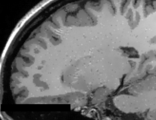

This module offer a simple application to the Anisotropic Anomalous Diffusion (AAD) filter, which is able to increase the image SNR and preserve fine object's details around the image space. This method was studied on MRI structural images (T1 and T2), which other imaging modalities could be properly investigated in the future.